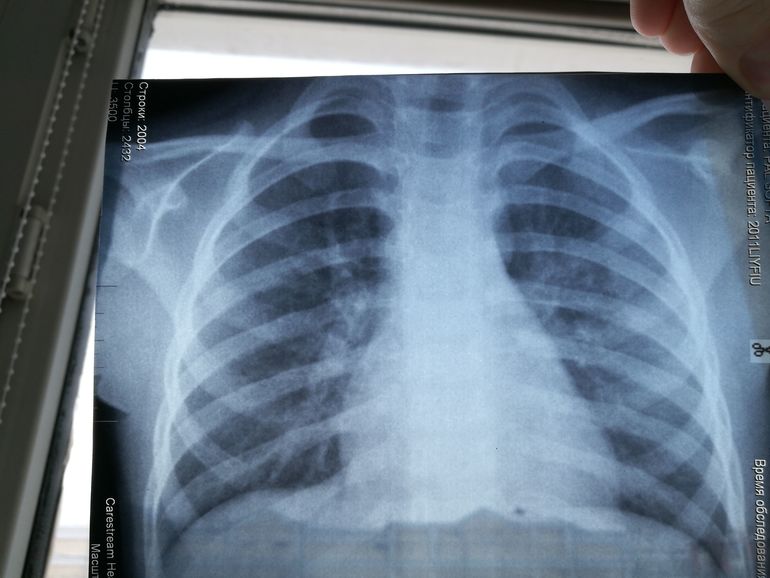

Рентгенодиагностика бронхопневмонии: Советы и примеры

Раздел: Альбом открытий